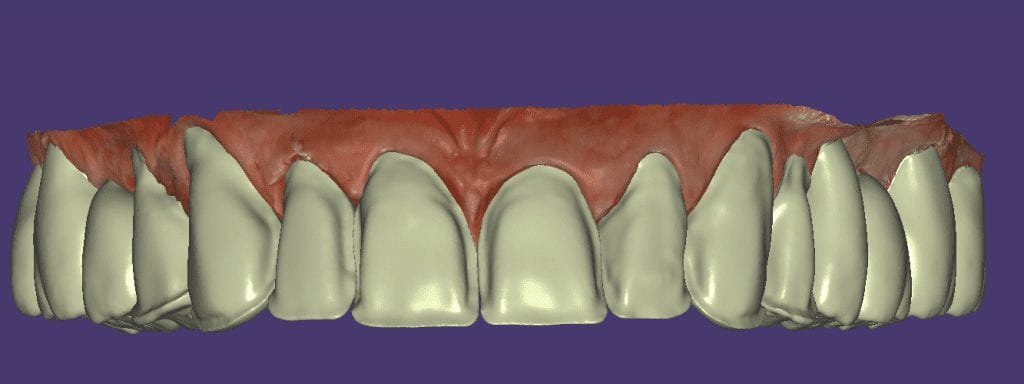

The digital models were then imported into a third party software where a library of tooth morphologies are available for the clinician to choose from.

Once the appropriate library is chosen, the digital wax ups are performed. In the subsequent photos you can see the transparent overlay of the wax-ups to the original position of the existing dentition

Once the case is designed to the ideal vertical dimension then multiple shells can be fabricated for treatment. The wax up model can be uniformly reduced by .5mmm’s circumferentially and a temporary shell can be designed. Once the teeth are prepared, these shells can be relined and seated onto the preps.